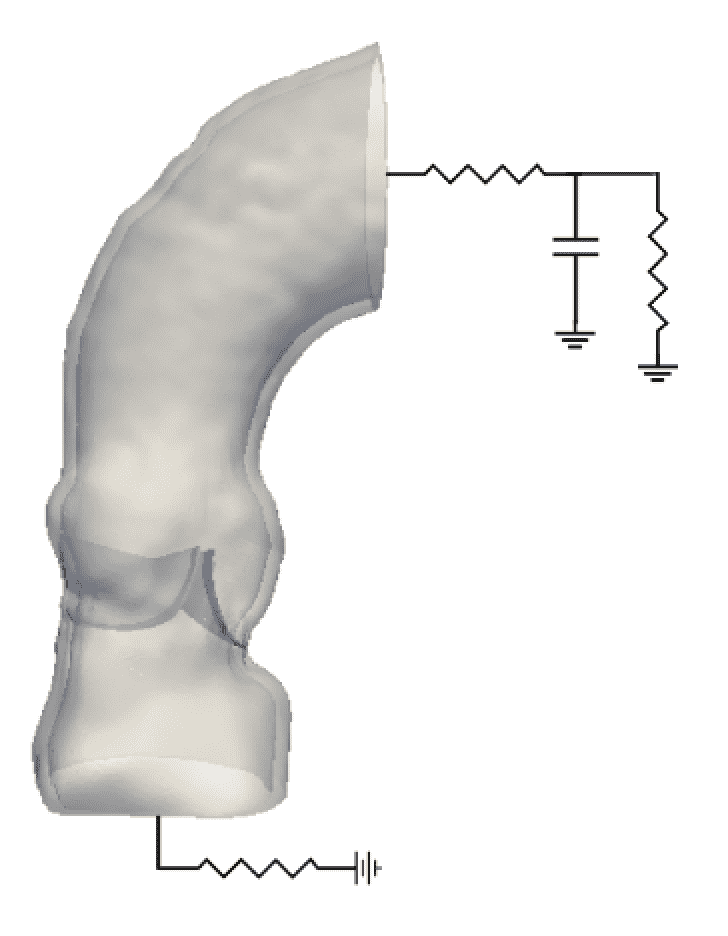

2.4 Driving and loading conditions

To drive flow through the model aortic root, we specify driving and loading conditions at the inlet and outlet using reduced-order models, as illustrated in Fig. 5. Let and indicate the inlet and outlet boundaries of the domain, and let and (respectively, and ) indicate the mean pressure and net flow rate along the inlet (respectively, outlet) boundary. At the outlet, we couple the three-dimensional FSI model to the three-element Windkessel model of Stergiopulos et al. [42] using an explicit coupling approach described previously [29]. Briefly, a first-order (Godunov) time step splitting is used to decouple the three-dimensional FSI model from the Windkessel model. The mean flow rate through the outlet surface, , computed by the three-dimensional FSI model is provided as an input to the Windkessel model. The pressure generated in the Windkessel model is used, along with the flow rate, to determine the pressure along the outlet surface, , which is used as a boundary condition for the three-dimensional model. See Griffith et al. [29] for further details. In our simulations, we use the “Type A” parameters from Stergiopulos et al. [42] fit to clinical pressure and flow rates collected by Murgo et al. [41]. At the inlet, we use a simple linear resistance model to drive flow, so that

| (16) |

with . This additional upstream resistance eliminates unrealistic ringing (i.e. the waterhammer effect) upon valve closure that otherwise occurs if . The upstream pressure waveform is determined from the “Type A” clinical pressure and flow rates collected by Murgo et al. [41].